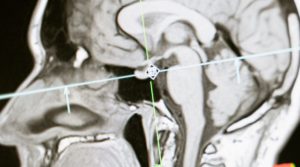

Copper could now be used for clearer MRIs

Story: Copper could now be used for clearer MRIs